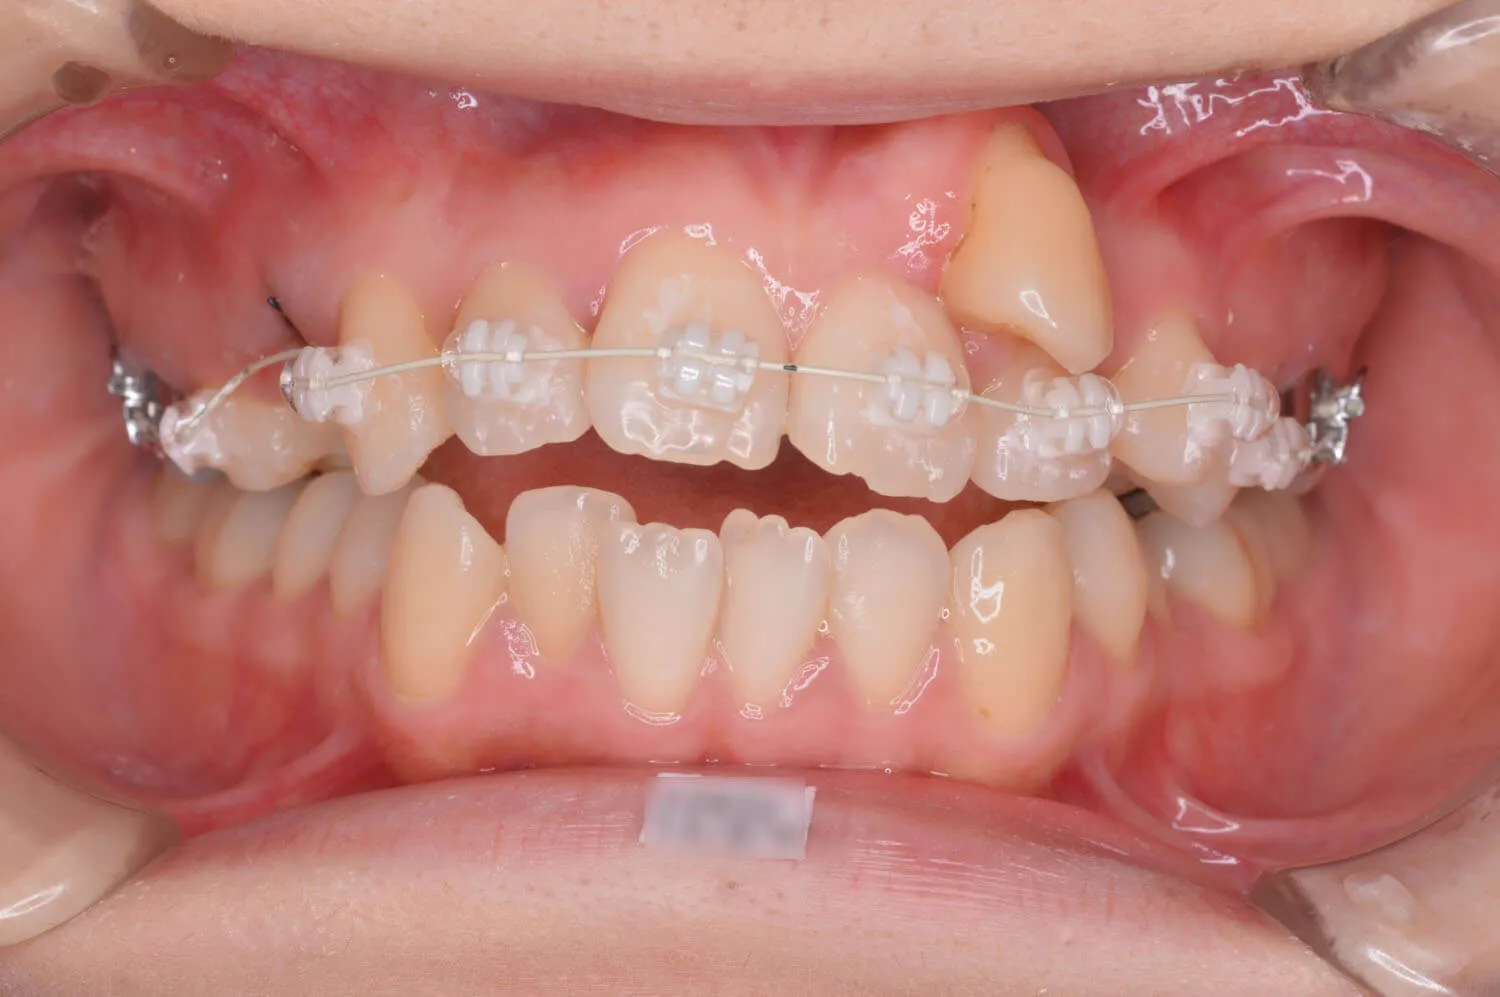

犬歯の位置が変わってきました。

犬歯が歯列に並んできました。